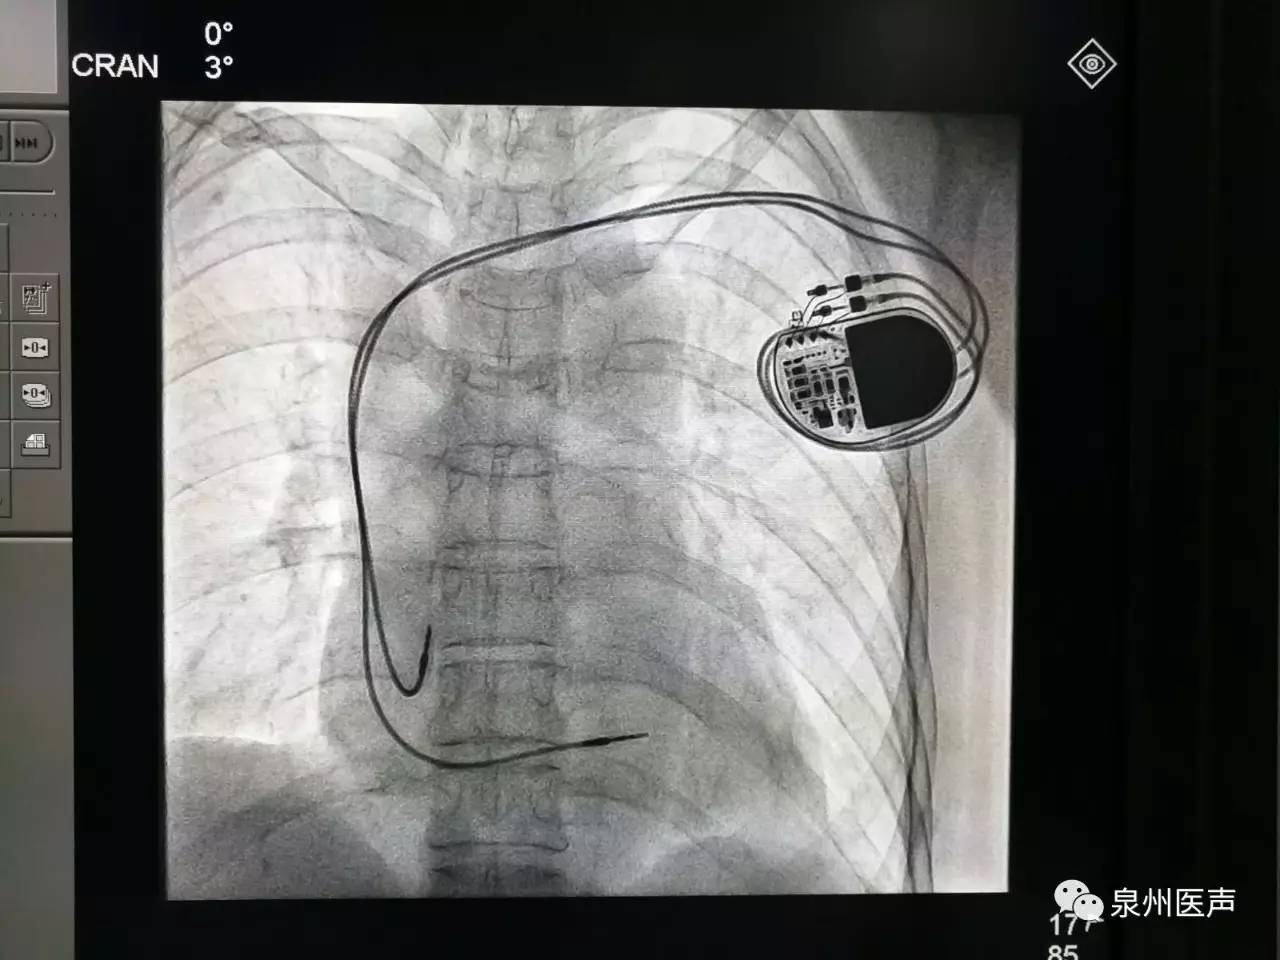

心臟起搏器的日常護(hù)理

心臟起搏器出院的宣教,是心內(nèi)科醫(yī)護(hù)人員不容忽視的一項(xiàng)工作